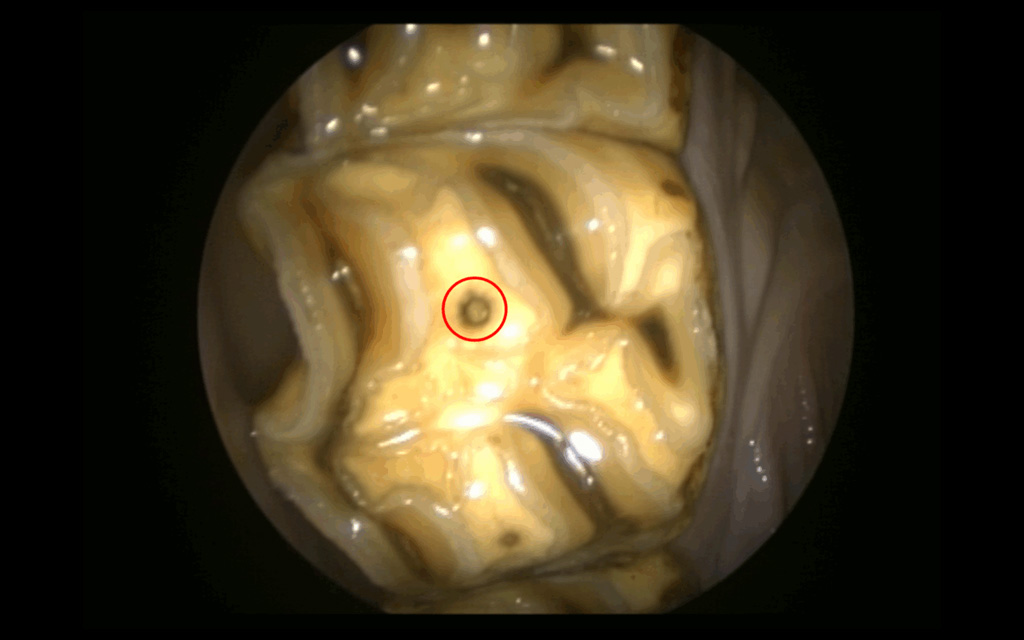

Oral endoscopy, tooth 109, abnormal pulp horn, occlusal fissure

Apical infection of tooth 109 with secondary sinusitis.

Radiographs showed abnormal pulp horns, an occlusal fissure, root shortening, and alveolar sclerosis, while CT revealed mucosal thickening in the maxillary sinuses, buccal wall discontinuity, and gas inclusions in the periodontal space and pulp chamber.